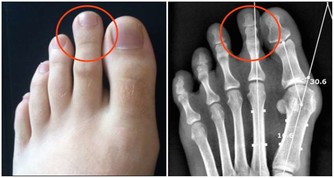

注意:

做之前註意先活動一下下肢,尤其是踝關節,提前做好熱身,可以避免在動作過程中出現不必要的傷害;注意保持平衡,避免摔倒。